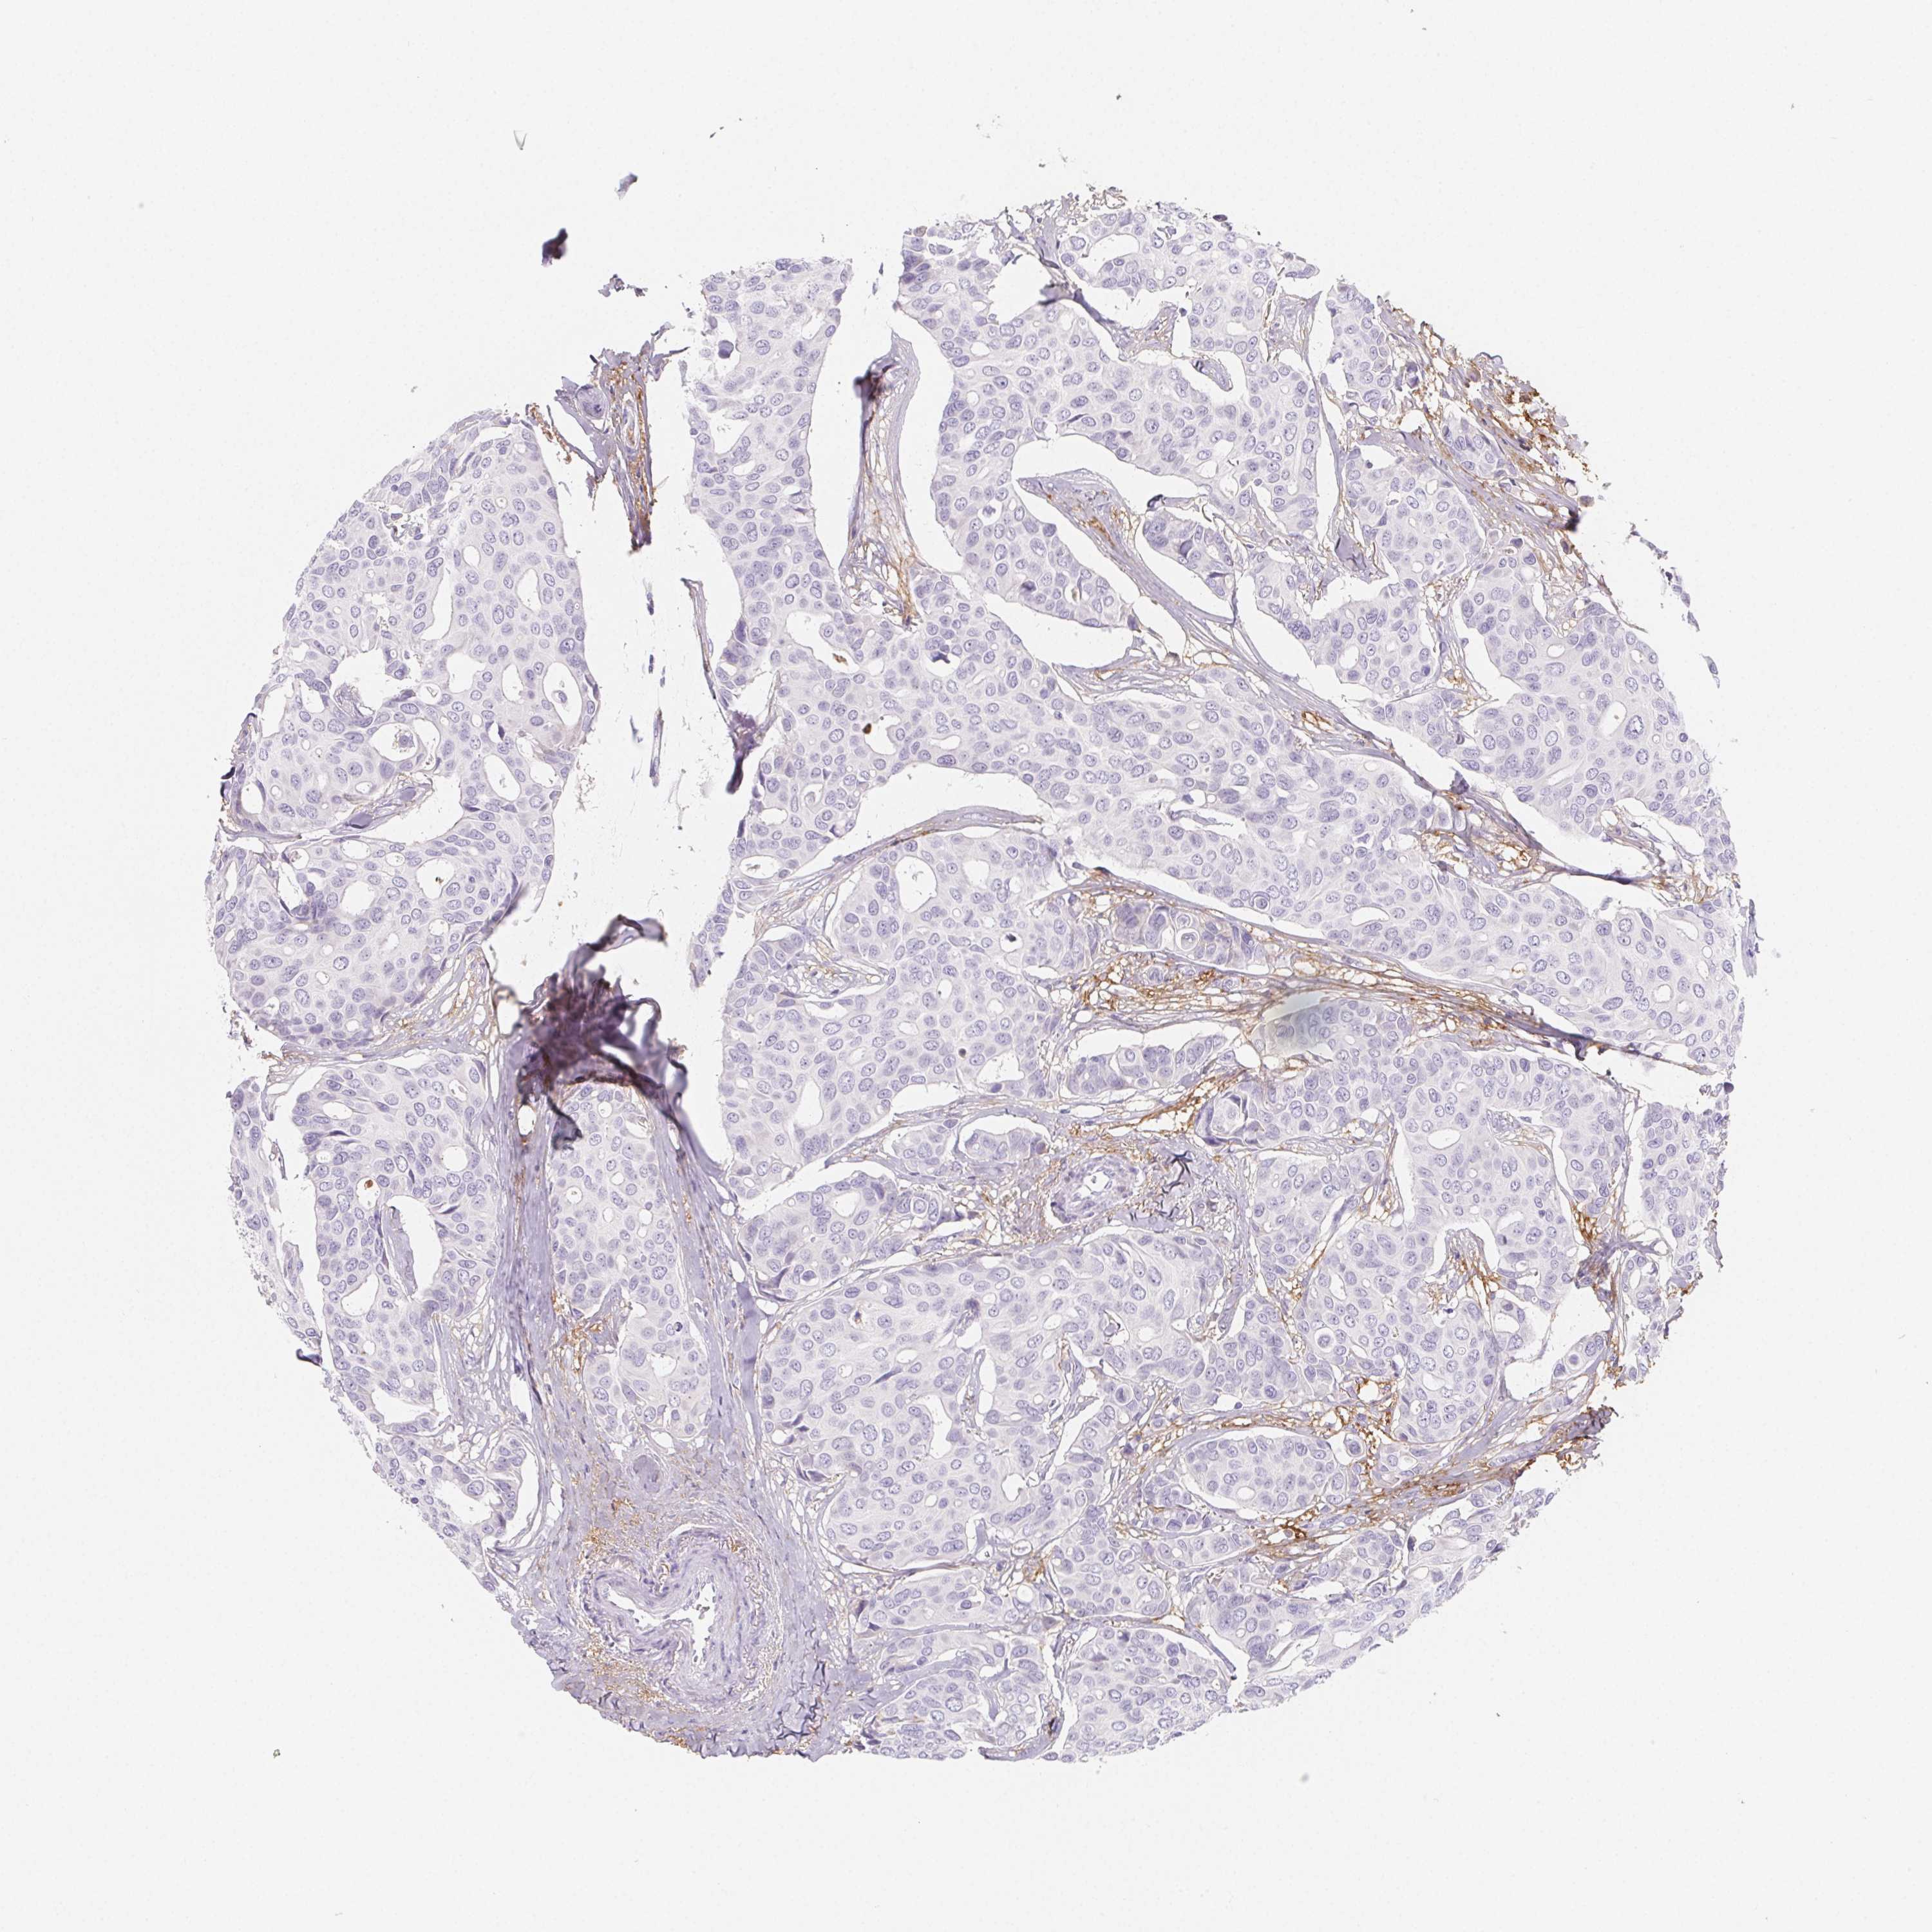

BRCA TCGA BRCA VALIDATION PROTEIN EXPRESSION

ANTIBODIES

AND

VALIDATION